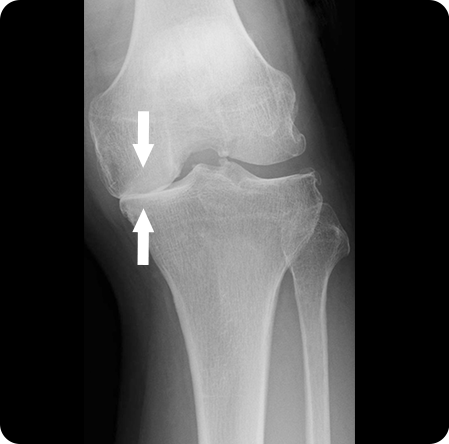

퇴행성관절염으로 연골이 마모되고 관절이 내려앉게 되어

진행된 휜 다리(O 다리, X 다리)를 바르게 교정하여

무릎 내 외측에 집중되어 있는 무게 중심을

고르게 분산시켜 관절염의 진행을 막는 수술법

입니다.